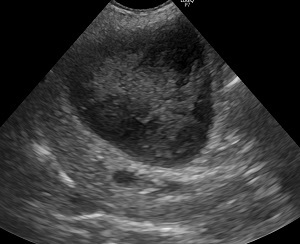

超音波検査で胆嚢とその周囲の臓器(肝臓、膵臓、十二指腸など)の状態を確認します。

腹部超音波検査: 胆嚢内に特徴的な「キウイフルーツ」や「星空」のような模様を持つ粘液が観察されます。これは診断において最も重要な検査です。